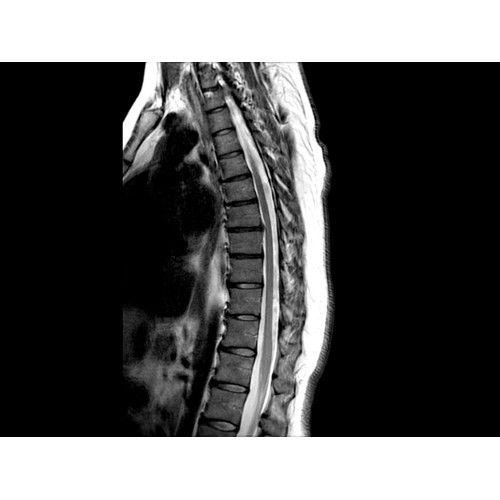

• Визуализация всего позвоночника слиянием двух участков — получить изображение всего позвоночника можно намного быстрее.

МР-томограф Optima MR450w позволяет получать изображения исключительно высокого качества, которые помогают установить диагноз. Чтобы удовлетворить ожидания клиентов в отношении высокого качества, в МР-томографе Optima MR450w были сохранены дополнительные возможности платформы Discoverу, привнесшие в его работу универсальность и мощь.

• Градиентная подсистема eXtreme — мощная градиентная подсистема для исследования тела характеризуется градиентом 34 мТл/м и скоростью нарастания градиента 150 Тл/м/с по каждой оси, что обусловливает быстроту, точность и высокую воспроизводимость сканирования.